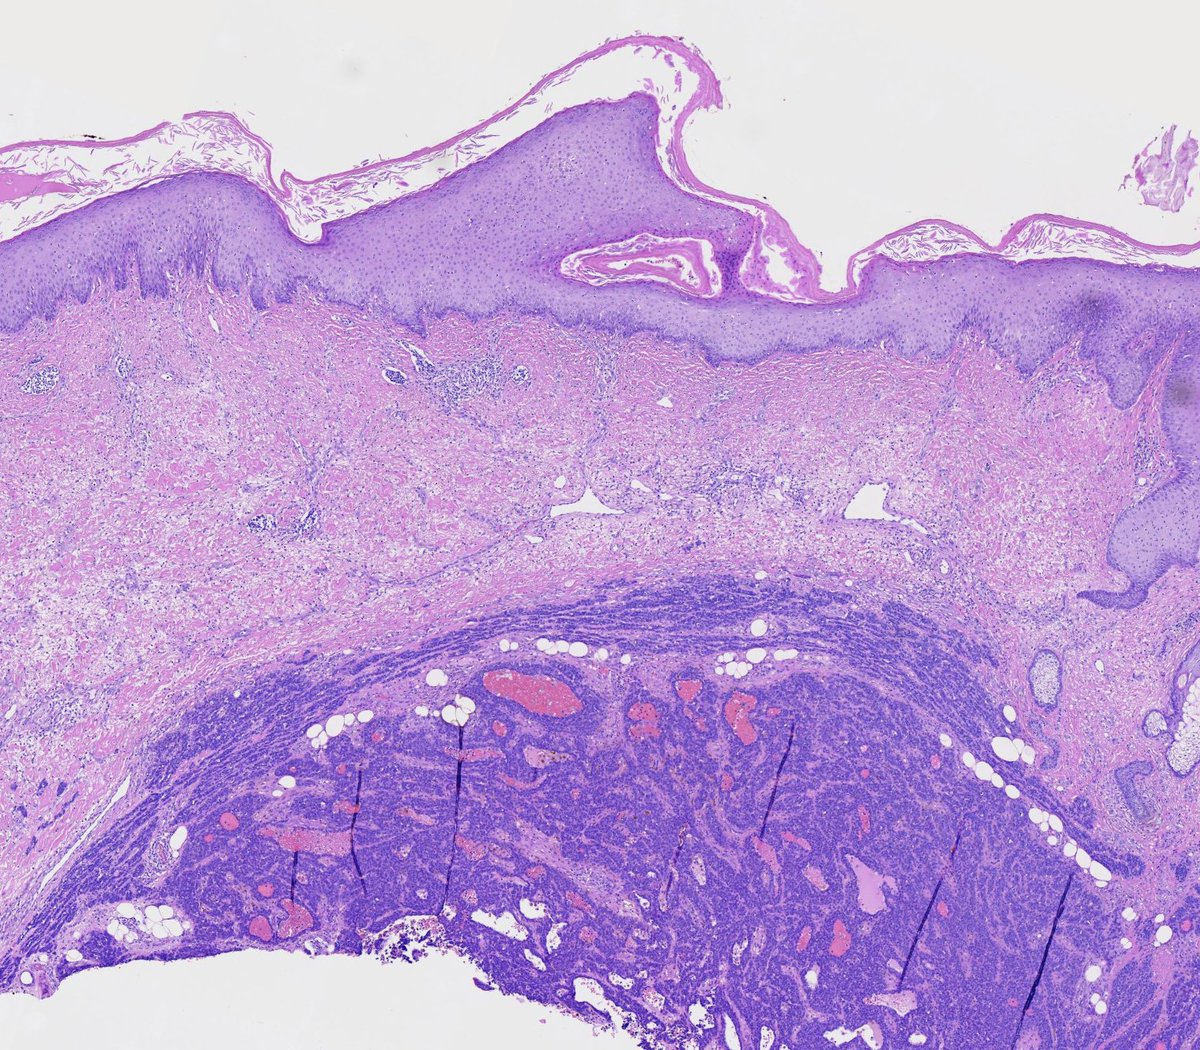

Couldn't be more excited to announce the launch of pathlibrary.com, the virtual slide site I wish had existed during my pathology residency. You can:

- See annotated histologic features